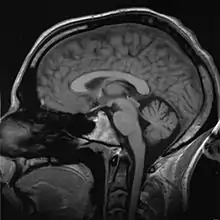

Medical/biomedical imaging is a major segment of medical devices. This area deals with enabling clinicians to directly or indirectly "view" things not visible in plain sight (such as due to their size, and/or location). This can involve utilizing ultrasound, magnetism, UV, radiology, and other means.

Imaging technologies are often essential to medical diagnosis, and are typically the most complex equipment found in a hospital including: fluoroscopy, magnetic resonance imaging (MRI), nuclear medicine, positron emission tomography (PET), PET-CT scans, projection radiography such as X-rays and CT scans, tomography, ultrasound, optical microscopy, and electron microscopy.